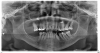

Digital radiography, since its introduction in the mid-1980s, has overtaken conventional screen-film radiography, making it one of the most significant advancements in the dental industry.3 It allows dental offices to acquire a quality image within a matter of seconds (Figure 1). It is a valuable, reliable diagnostic tool for patients of all ages. In children, for example, the primary reasons radiographs are used are for the detection of caries, dental injuries, disturbances in tooth development, and the examination of pathologic conditions other than caries.4 Additionally, 3-dimensional reconstruction of radiographic images is of importance for diagnosis and treatment planning concerning malformations, trauma, tumor investigation, and surgery planning.

Fig 1. Digital radiography allows dental offices to acquire a quality image within seconds.

Figure 1